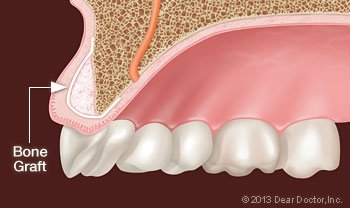

Bone grafting is a minor surgical procedure that is normally done in a dental office. An incision is made in your gum to gain access to the bone beneath it, and then grafting material is added. Most often, the grafting material is processed bone minerals around which your body will actually deposit new bone cells.

The grafting material itself can come from your own body, but very often it is bone from an animal or human donor that has been treated by a laboratory to make it sterile and safe. It can even be a synthetic substance. Grafting material comes in a variety of forms: powder, granules, putty or a gel that can be injected through a syringe. The graft, which is generally covered by a collagen membrane for optimum bone repair, will act as a scaffold onto which your body will build new bone.